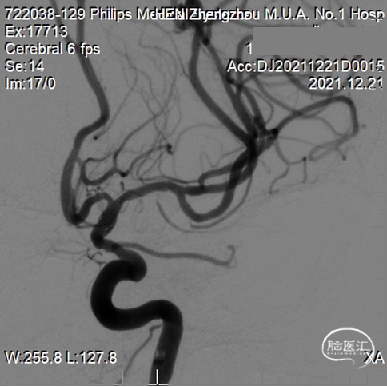

6个月复查

从6个月复查结果看到大脑中动脉穿支似乎较术前和术后即刻DSA有所减少,希望术者解释其原因并提供更多的动态影像信息,提供随访磁共振影像和临床随访结果。